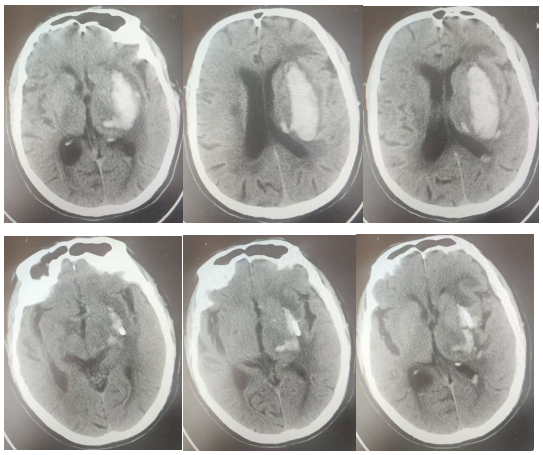

术前头颅CT及术后第一天复查头颅CT对比

手术中,团队首先通过机器人系统完成患者头颅CT三维重建,精准规划穿刺路径,将误差控制在1毫米以内,有效避开了颅内重要血管与神经。在机器人精准引导下,可视化引流管直达血肿核心,医生可通过屏幕实时监测血肿清除过程,实现全程可视化操作,最终精准抽吸出约30ml积血。手术全程仅40分钟,切口仅2-3mm,创伤极小、术中出血少。术后复查CT显示,血肿基本完全清除,引流管位置精准无误。患者意识迅速恢复,右侧肢体肌力显著改善,无新发神经功能障碍,目前已进入康复阶段。